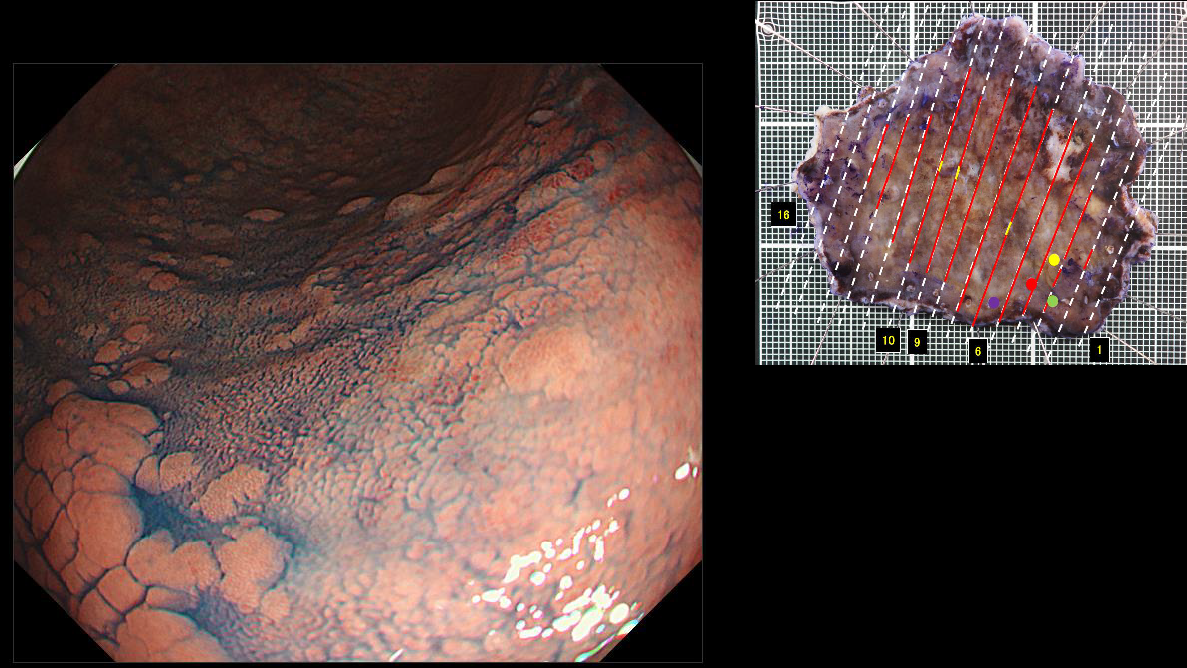

ホーム > 診療科・部門案内 > 消化器センター 消化器内科 > 消化管Mapping > 消化管Mapping~胃~ > 消化管Mapping~胃~ 2025.9.10